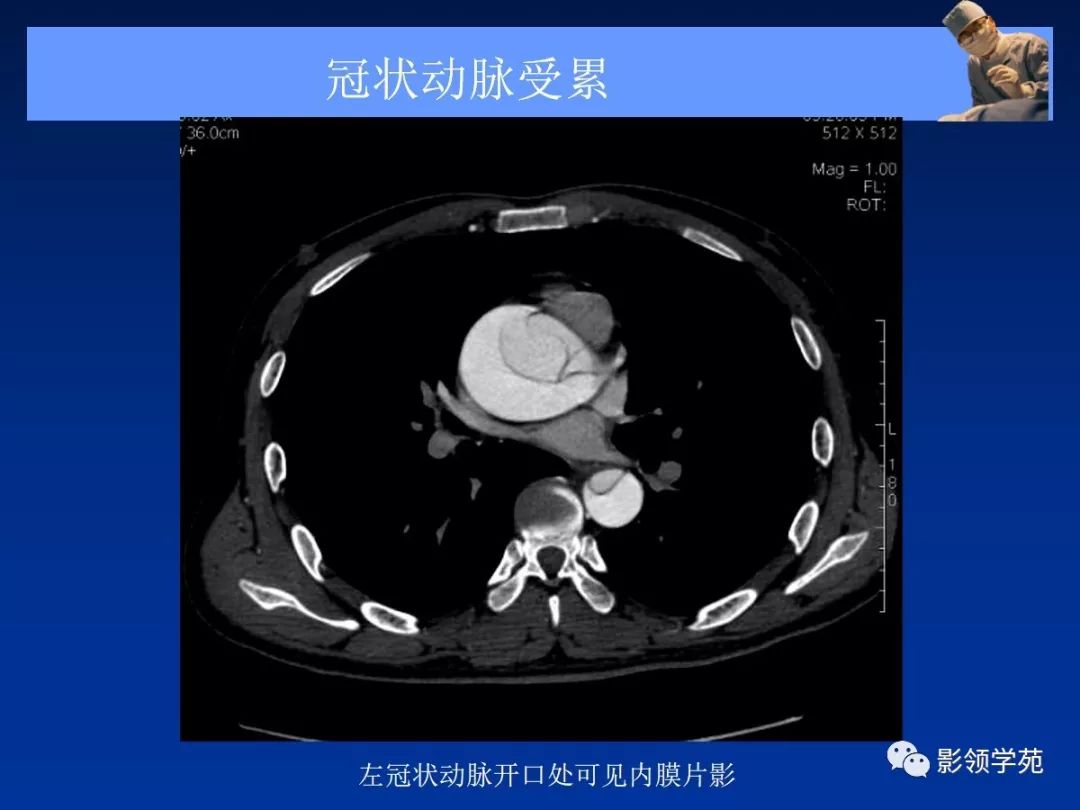

典型AD:

病理学特点:

- 内膜撕裂

- 真假“双腔” ,存在交通